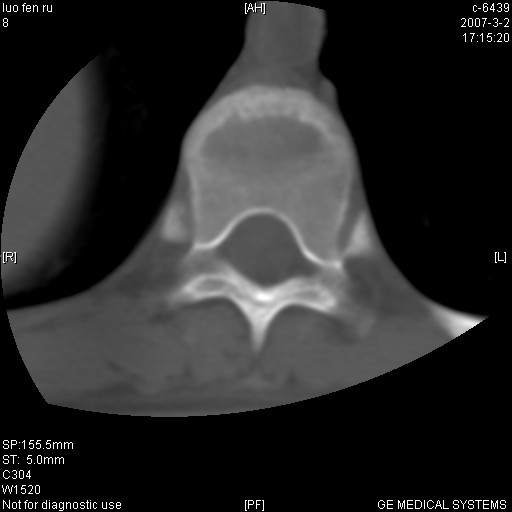

标题: CT6952:T11椎体病变请讨论

女,19岁.背部疼痛一月余.自诉幼时有个外伤史.

陈旧性骨折,有侧位片参考一下更好。

腰椎平片示,t11椎体呈楔形改变,椎间隙未见异常.

当是应是椎体(前半部较厉害)压缩性骨折,这就印证了这就是陈旧性骨折。

病人病史不长,病变表现比较明显,如果是结核,病史不支持,椎间隙不窄,临近椎体正常,椎旁无冷浓疡,但从病变本身硬化也较多,均不太支持结核。慎重考虑的话,可以问一下病人有无结核病史。如果没有,更多的应该考虑陈旧性骨折,伴有慢性椎间盘炎可能。确诊后记着告知啊!

t11椎体前缘不规则形骨质破坏,周围有硬化边,软组织肿块不明显,首先考虑:骨嗜酸性肉芽肿 。期待随访结果。